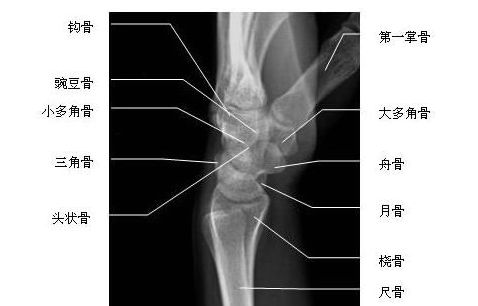

腕关节侧位-X线图

腕关节侧位-X线